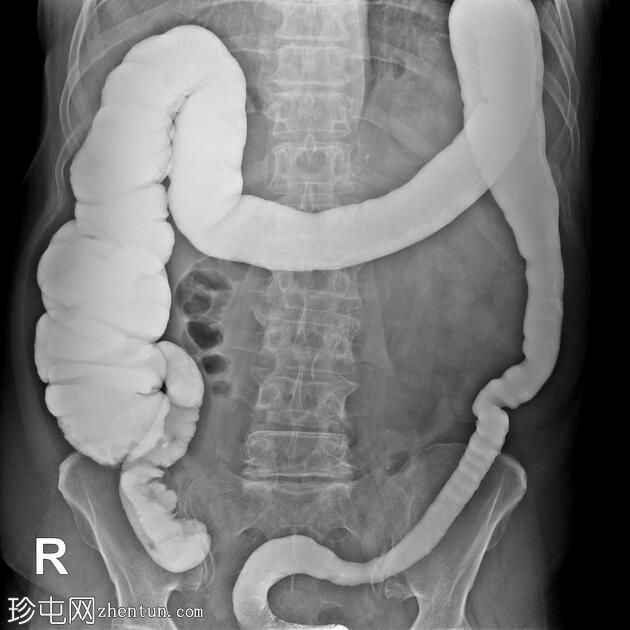

结肠异常表现包括结肠袋皱襞消失,使其外观模糊,呈铅管样改变。

其他异常表现包括降结肠和乙状结肠肠袢狭窄,以及横结肠和降结肠多处黏膜糜烂(双对比增强图像可见)。

未见肿块或瘘管形成。

升结肠外观正常,结肠袋皱襞完整。

结肠镜检查和活检结果显示为溃疡性结肠炎,属于炎症性肠病。

结肠呈铅管状外观是慢性炎症性肠病(溃疡性结肠炎)的典型放射学表现。